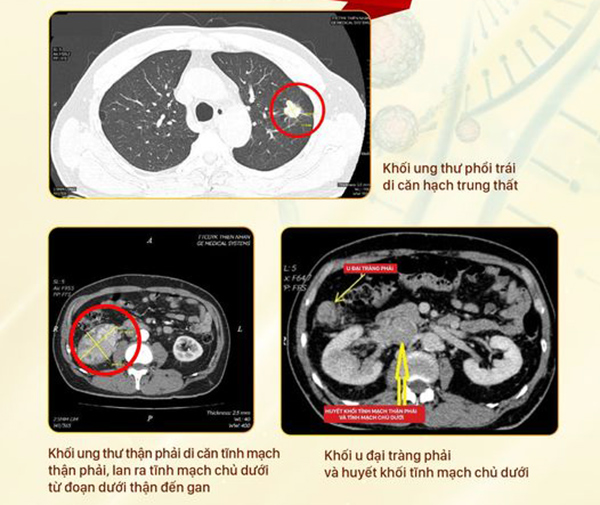

DNVN - Bệnh nhân N.X.C (71 tuổi) đến Trung tâm Chẩn đoán y khoa kỹ thuật cao Thiện Nhân Đà Nẵng khám sức khoẻ vì thấy khó thở thì phát hiện bị cùng lúc 3 khối ung thư riêng biệt. Kết quả chụp PET/CT sau đó tại Singapore cũng hoàn toàn trùng khớp!